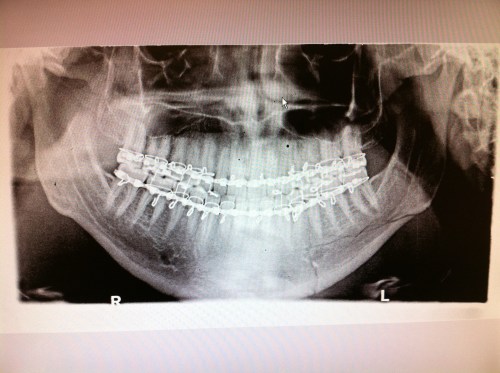

We went to the doc yesterday so they could see how my jaw looks a couple days after being patched back together. Here’s how the x-rays looked. You can see the multiple breaks on the right side of the image.